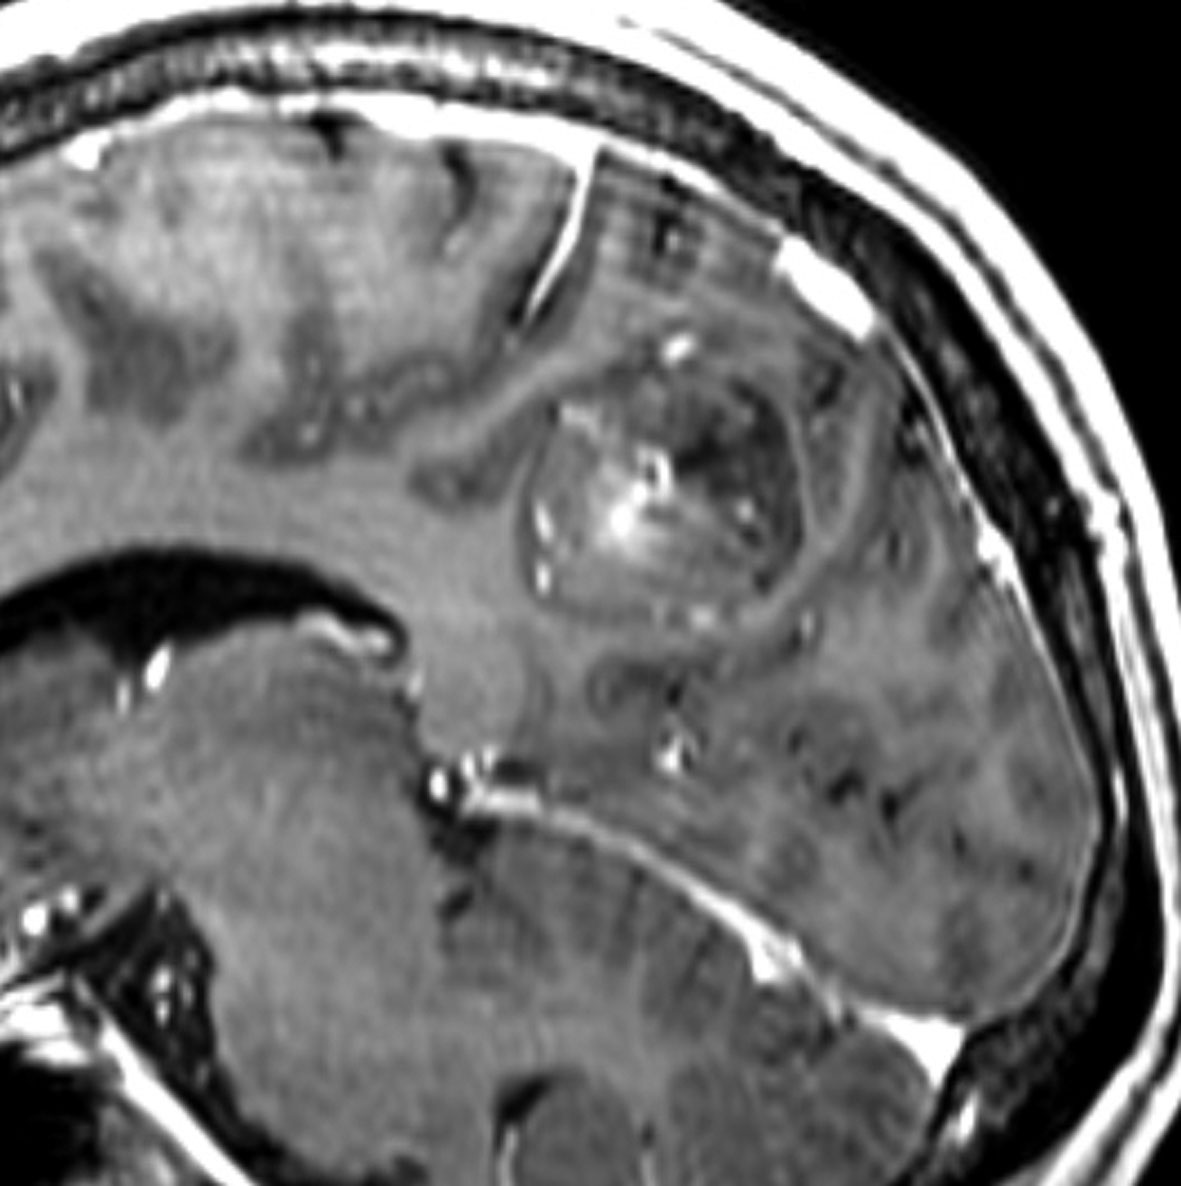

神経節細胞腫は放射線治療抵抗性

Tourette syndrome(音声と行動のチック,不随意運動)で発症した男児です。石灰化もありのう胞も伴う大脳基底核gangliocytoma grade 1で,摘出にはリスクがあると判断して46グレイ23分割の定位放射線治療をしました。しかし治療抵抗性で増大したために,上側頭溝からの経路で腫瘍を摘出(右の画像)しました。それ以来13年が経ちますが再発はありません。グレード1の神経節細胞腫は放射線治療抵抗性のものが多いと考えた方がいいし,より大きな線量を使用しても同じ結果なのでしょう。